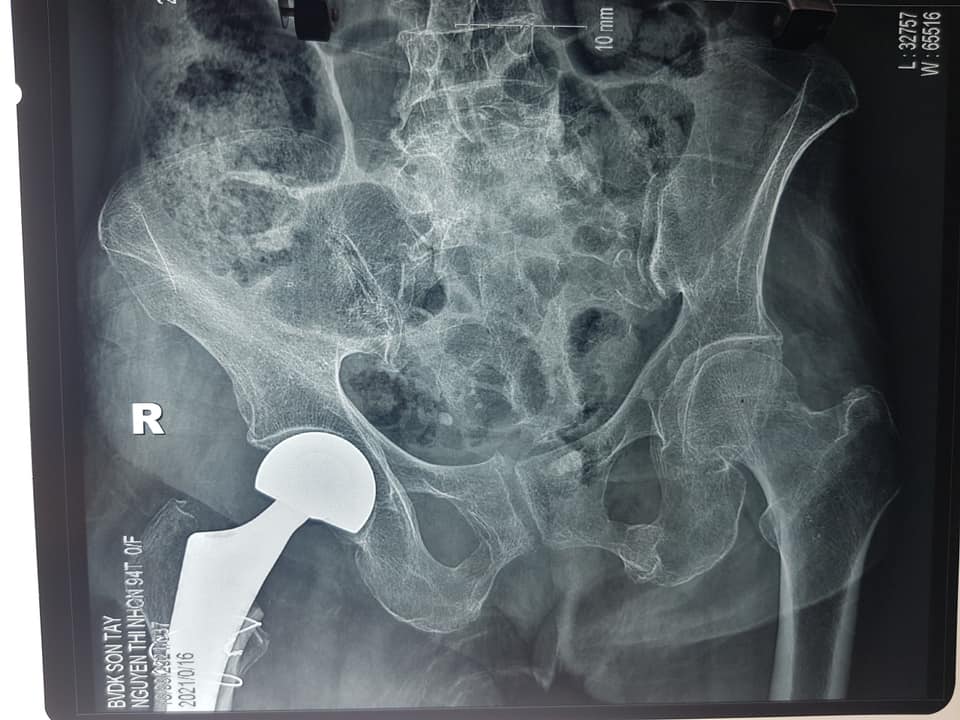

Trước đó, ngày 14/9/2021 bệnh viện cũng đã phẫu thuật thay khớp háng bán phần không xi măng cho bệnh nhân Nguyễn Thị N 94 tuổi ở tại Lê Lợi – Sơn Tây – Hà Nội.

Hiện tại sức khỏe hai cụ ổn định, ngồi dậy vận động tốt, vết mổ liển tốt, ăn uống tiêu hóa tốt.